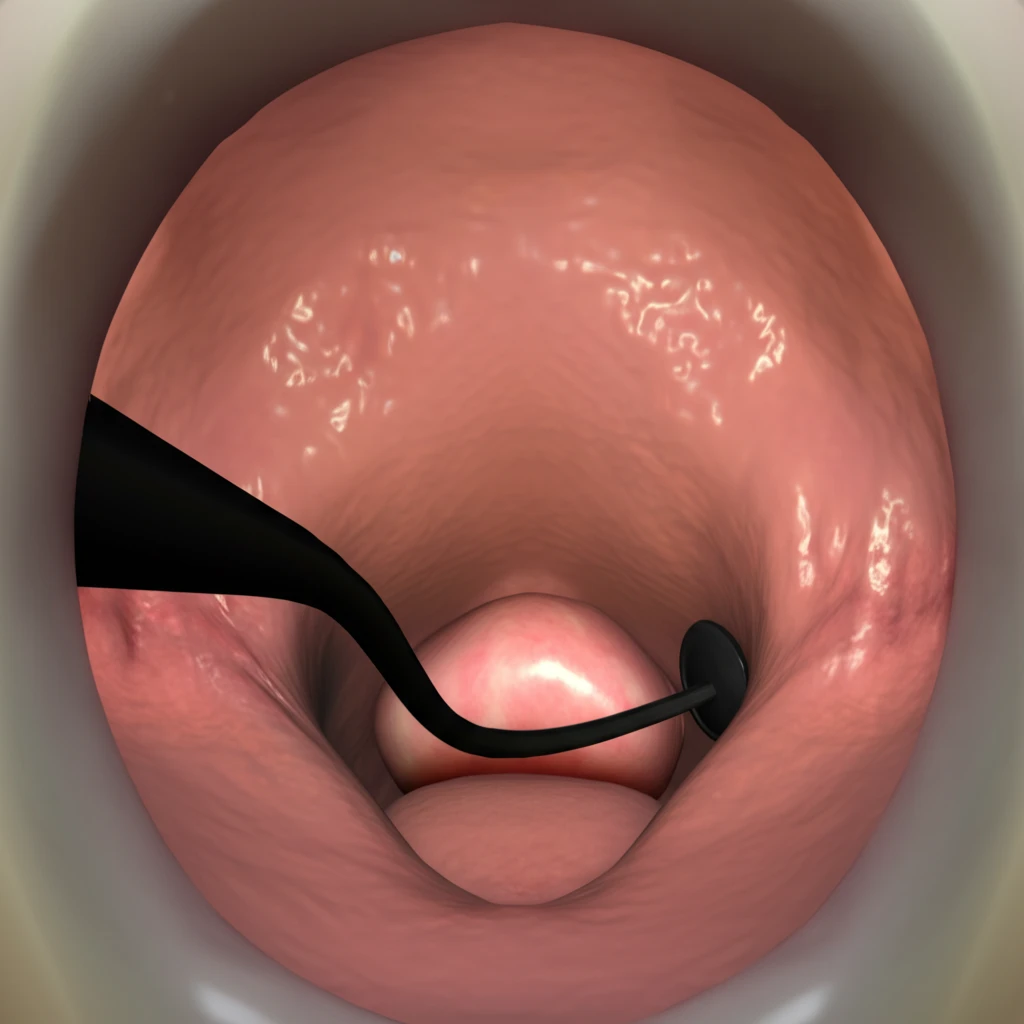

후두내시경 검사는 후두를 효과적으로 관찰하기 위해 크게 두 가지 방법으로 나뉘며, 각각의 특징과 적용 대상이 다릅니다.

- 직접 후두경 검사:

- 후두경이라는 특수 기구를 입 또는 코를 통해 삽입하여 후두를 직접적으로 관찰하는 방법입니다.

- 보다 정밀한 관찰이 가능하며, 필요에 따라 조직 검사나 간단한 시술(예: 이물질 제거)을 동시에 진행할 수 있습니다.

- 직접 후두경 검사는 다시 경직형과 연성형으로 나뉘며, 연성형은 코를 통해 삽입하여 환자의 불편감을 최소화합니다.